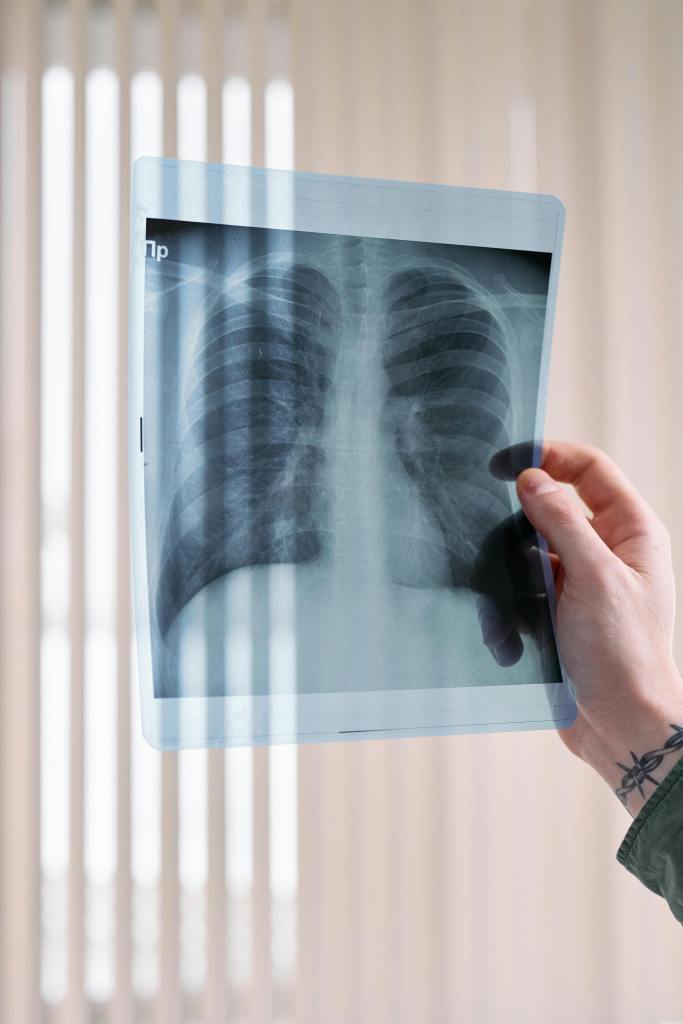

Imaging:

• TC encefalo

• AngioTC dei vasi intra ed extra cranici

• RM encefalo smdc o con mdc

• Flussimetria

• RM funzionale di perfusione

• TC e RM rachide

• AngioRM

• RM e TC orbite e rocche petrose

• RM e TC temporo-mandibolare